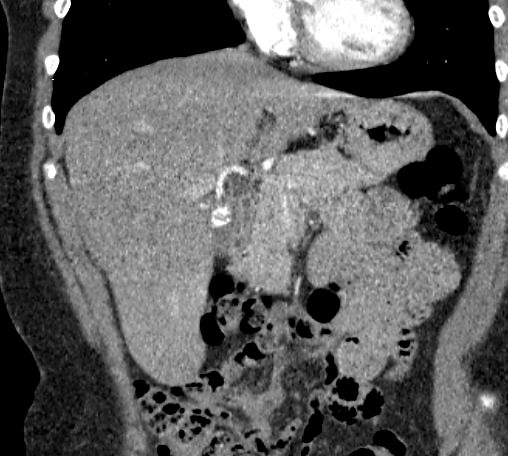

Мультиспиральная компьютерная томография (МСКТ) брюшной полости и забрюшинного пространства относится к современным лучевым методам исследования, с помощью которого можно оценить состояние органов брюшной полости (печени, желчного пузыря, поджелудочной железы, селезенки), забрюшинного пространства с расположенными в нем почками, надпочечниками, мочеточниками и прилегающих к ним кровеносных сосудов и лимфатических узлов.

С помощью мультиспиральной компьютерной томографии проводятся послойные рентгеновские снимки исследуемой области с толщиной среза от 0,5 мм. Затем полученные данные преобразуются в цифровые трехмерные модели органов и систем в мельчайших подробностях.

При подозрении на опухоли, воспалительные процессы, гнойные очаги назначается КТ брюшной полости и забрюшинного пространства с внутривенным болюсным контрастированием. Для этого пациенту внутривенно вводится рентгеноконтрастное вещество на основе йода. Благодаря усиленному кровоснабжению, которое обычно наблюдается в патологических очагах, препарат накапливается в структуре патологических образований и помогает врачу-рентгенологу выявить изменения внутренних органов.

Метод контрастирования помогает максимально точно выявить очаг патологии уже на начальной стадии, а также установить его локализацию, точные размеры, форму и особенности кровоснабжения. Возможности мультиспиральной компьютерной томографии позволяют выполнить своевременную диагностику заболеваний внутренних органов, от чего напрямую зависит эффективность лечения.